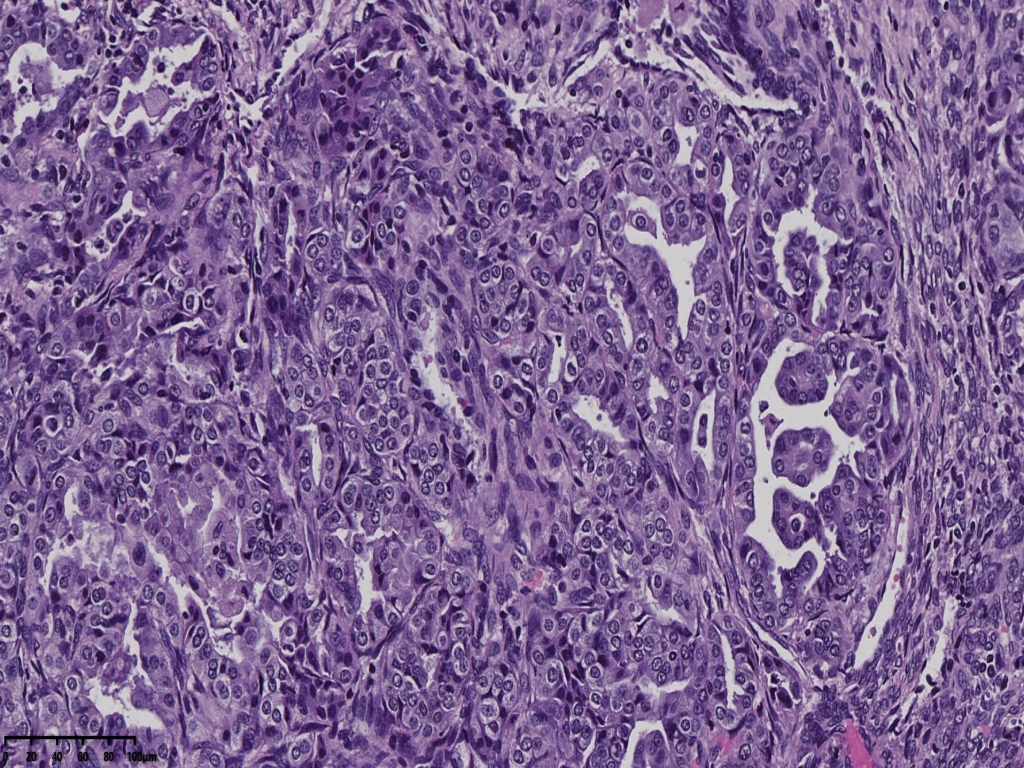

镜下可见肿物,腺样机构,密集,细胞异型

局部分区域腺体偏实性,细胞核大,周围胞浆空亮,会诊为子宫透明细胞癌,是不是就依据这一点?

但是其余部位内膜可见微乳头结构。

宫颈管及宫颈管可见癌组织侵犯浅层,以腺样结构为主

癌组织侵及子宫壁浅层,小于1/2,累及宫颈浅层。